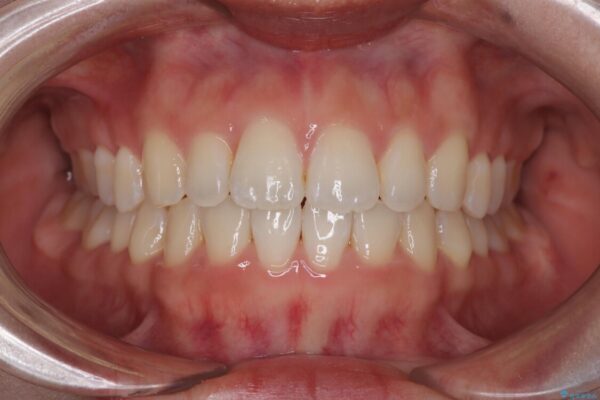

治療終了時

前歯が自然なアーチにきれいに並び、正中(上下の中心線)も整い、咬み合わせも良好です。

側方拡大することで、非抜歯であるにも関わらず前歯が前方に出ることなく、バランスの良い仕上がりとなりました。

治療後

• 目立ちにくい表側装置で1年完了!狭いアーチを側方拡大し前歯のデコボコを整えた症例 治療後画像